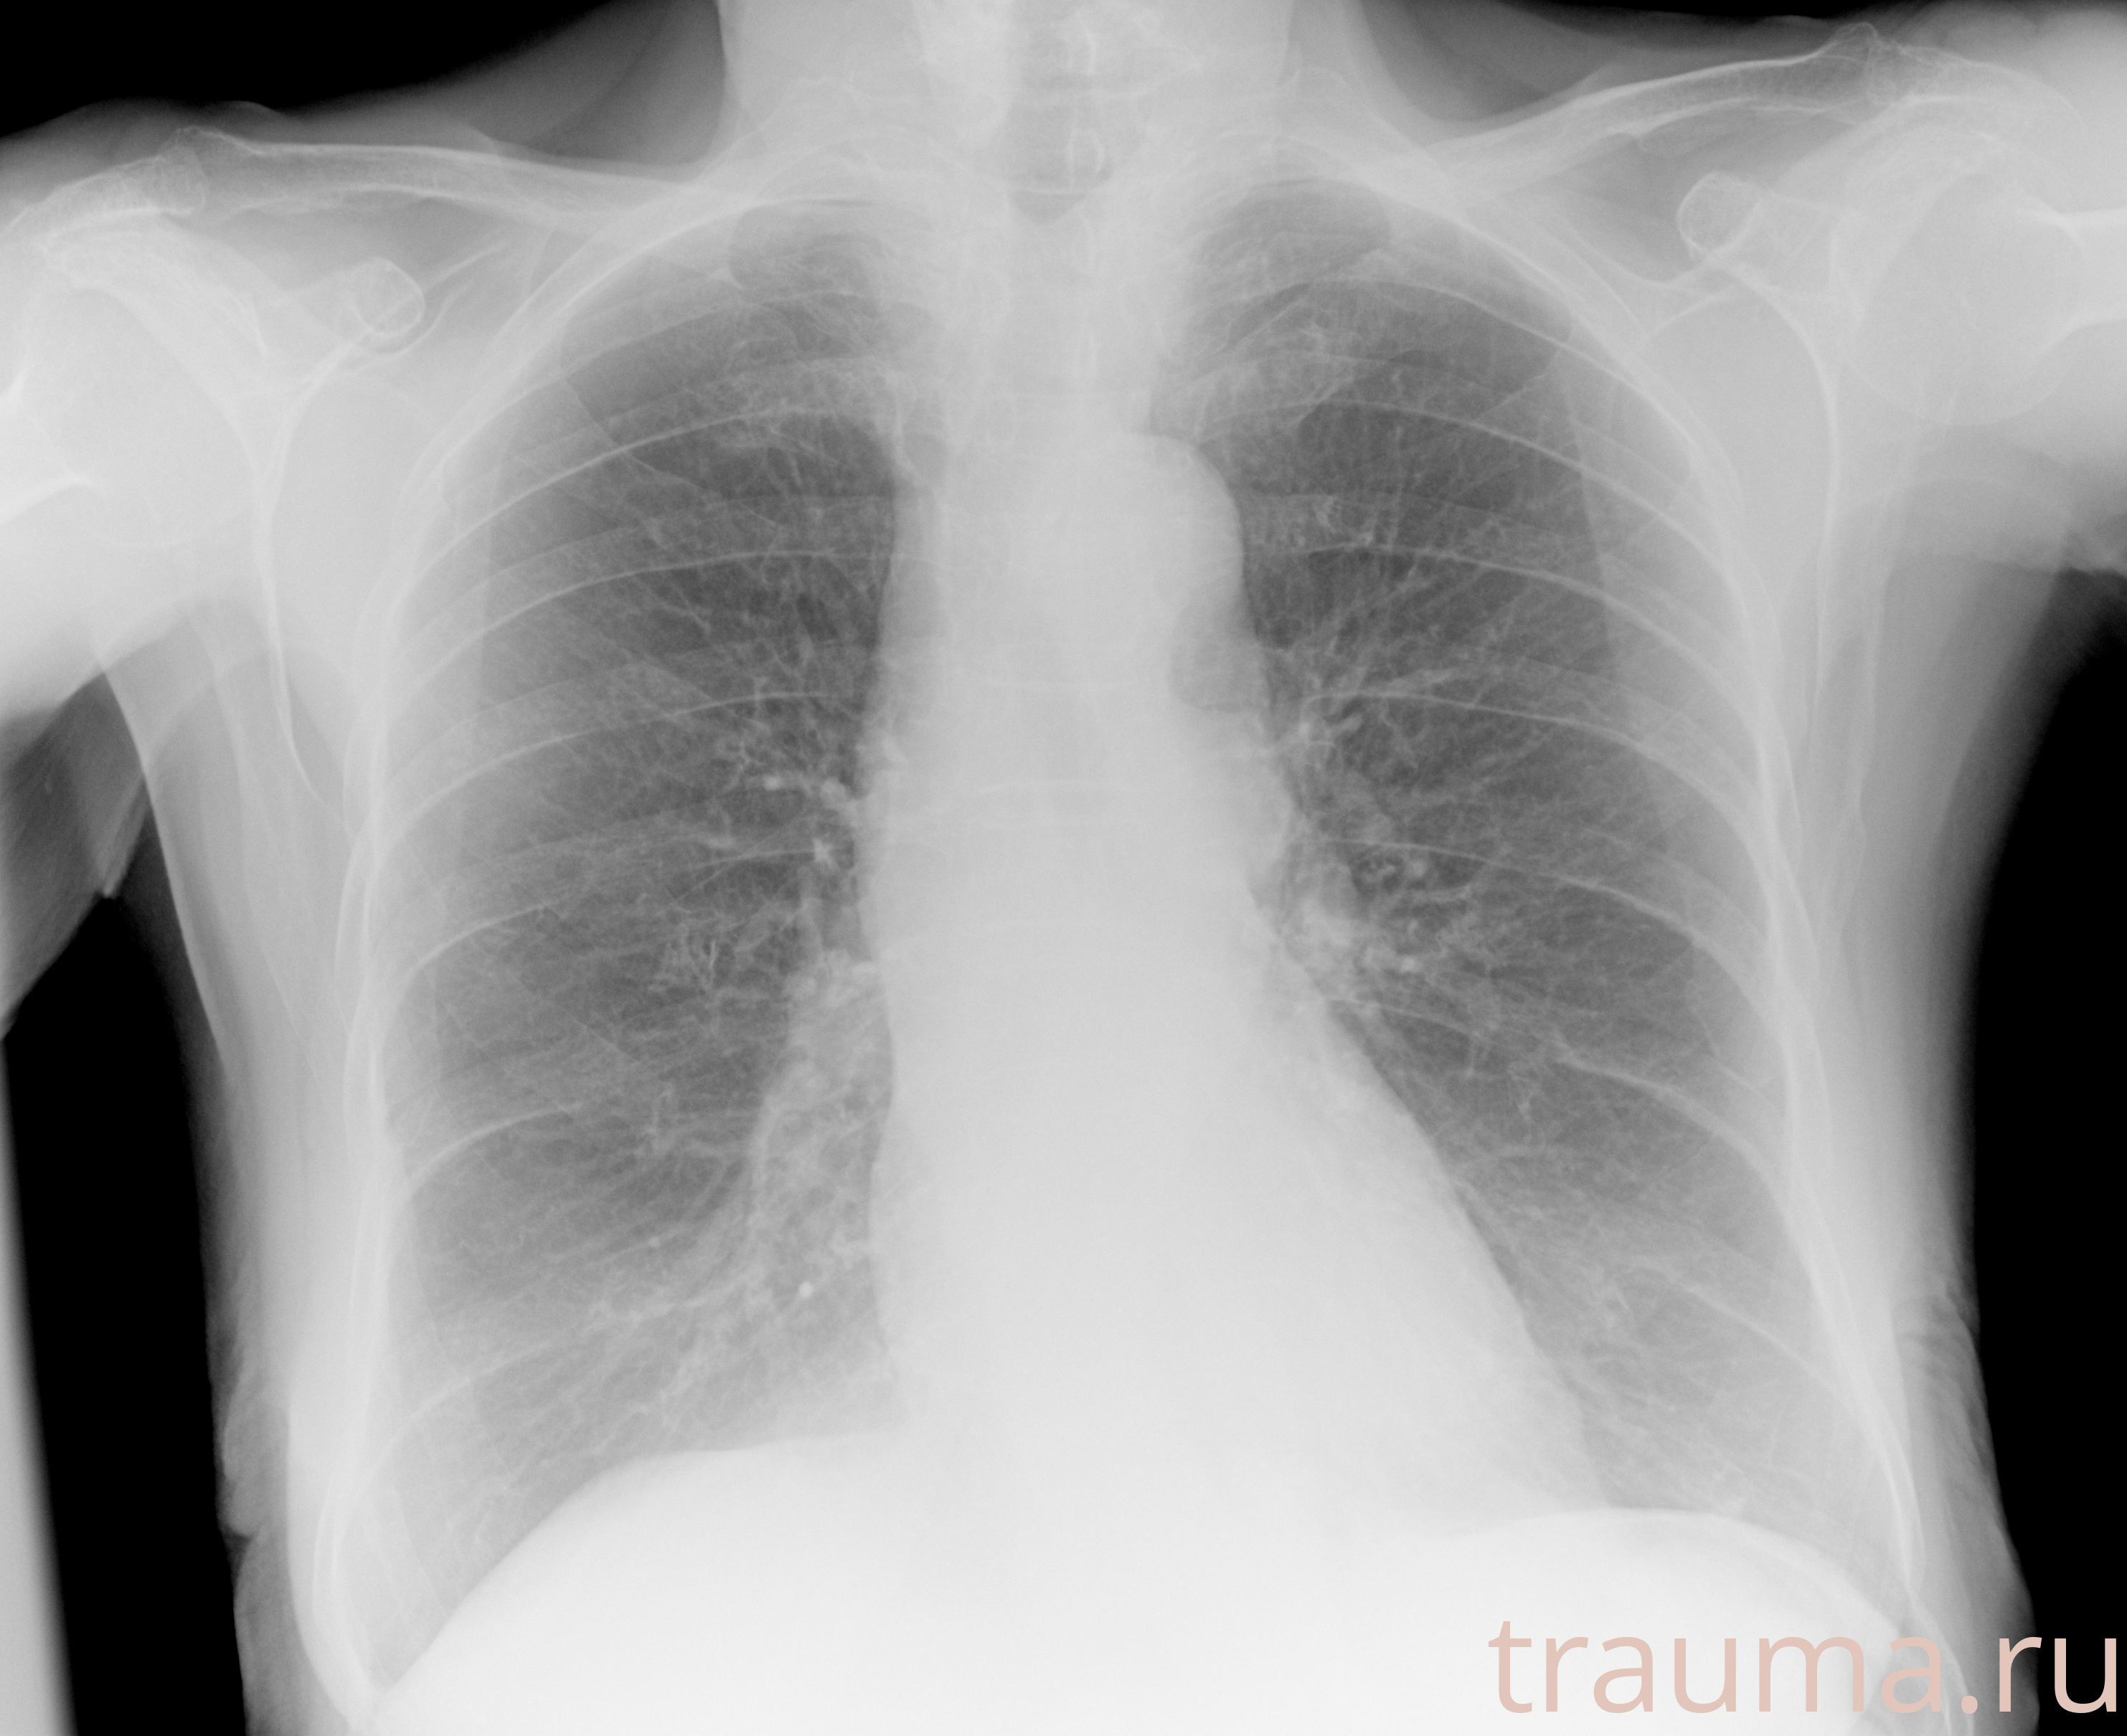

Рентгенограммы

Рентген на дому: по вашему адресу приезжает врач-рентгенолог, травматолог-ортопед с мобильным рентгеновским аппаратом, проводит диагностику травмы или заболевания, делает необходимые рентгенограммы, дает рекомендации по дальнейшему лечению. Получить качественные снимки в домашних условиях возможно благодаря уникальной методике, разработанной МосРентген Центром для института  Склифосовского

при переломе шейки бедра и пневмонии от компании МосРентген Центр - партнера Института имени Склифосовского